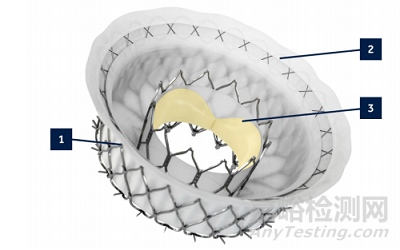

LuX-Valve (Plus)(健世科技)

LuX-Valve 經(jīng)導(dǎo)管介入三尖瓣置換系統(tǒng)是寧波健世研發(fā)的經(jīng)右心房植入介入三尖瓣自膨脹生物瓣膜,是中國唯一一款獲得美國藥監(jiān)局 FDA 授予的突破性器械認(rèn)定的結(jié)構(gòu)性心臟病領(lǐng)域醫(yī)療器械,已進(jìn)入 NMPA 創(chuàng)新醫(yī)療器械特別審查程序,預(yù)計(jì)將在 2023 年進(jìn)入市場(chǎng),有望成為全球首款獲批上市的三尖瓣置換介入治療產(chǎn)品。LuX-Valve 選用抗鈣化處理的牛心包三葉瓣,聚四氟乙烯(ePTFE)覆蓋的自膨脹鎳鈦合金的瓣膜支架(如下圖 A-c),室間隔錨定器(如下圖 A-a)以及 2 個(gè) ePTFE 覆蓋的夾持鍵(如下圖 A-b)。該產(chǎn)品采用全球首創(chuàng)的“非徑向支撐力依賴“和“室間隔固定”的設(shè)計(jì)理念,通過前瓣夾持鍵和室間隔錨定針進(jìn)行固定,避免了對(duì)瓣環(huán)周圍結(jié)構(gòu)的損傷。同時(shí),與徑向力錨定裝置相比,LuX-Valve 不影響 TR 消除后的瓣環(huán)回縮以及右心室結(jié)構(gòu)重構(gòu),對(duì)瓣環(huán)無徑向力壓迫,沒有植入后引起冠狀動(dòng)脈損傷、房室傳導(dǎo)阻滯的風(fēng)險(xiǎn)[69]。更重要的是,三尖瓣置換臨床痛點(diǎn)在于外科手術(shù)高危的極重度 TR 患者的瓣環(huán)極大而無法采取介入治療,而 LuX-Valve 最大瓣環(huán)直徑達(dá) 65-75mm,即使是被海外所有 TTVr 和TTVR 篩敗的患者,LuX-Valve Plus 入選率仍高達(dá) 19/20,極大程度上擴(kuò)大了適應(yīng)癥范圍。LuX-Valve 最主要的問題是在于其心房盤片有血栓形成,不過目前還未出現(xiàn)肺栓塞的情況,血栓的形成與預(yù)后的關(guān)系還有待驗(yàn)證。另外,第一代 LuX-Valve 為經(jīng)胸切口輸送,第二代經(jīng)頸靜脈入路產(chǎn)品 LuX-Valve Plus 正在開展全球多區(qū)域臨床研究。

▲ LuX-Valve 三尖瓣置換系統(tǒng)及其植入示意 (資料來源:First-in-Man Experience of Transcatheter Tricuspid Valve Replacement With LuX-Valve in High-Risk Tricuspid Regurgitation Patients. JACC Cardiovasc Interv. 2020 Jul 13 ,蛋殼研究院)